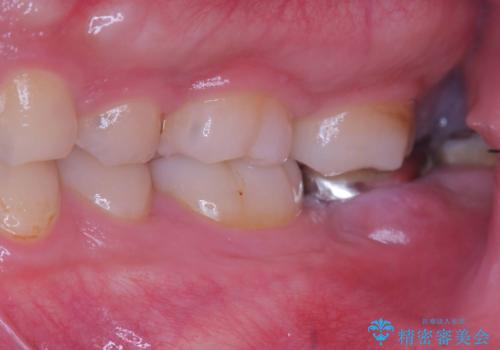

銀歯の下の虫歯|オールセラミッククラウン|歯を長持ちさせるための治療|歯の神経を守る

担当医 河野豊嘉